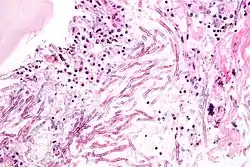

| H&E stain showing a fungal pneumonia (pulmonary aspergillosis) | |